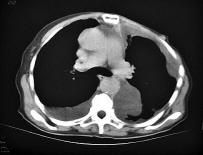

| Tràn dịch màng phổi trên phim chụp cắt lớp.Nguồn:ngoaikhoalamsang |